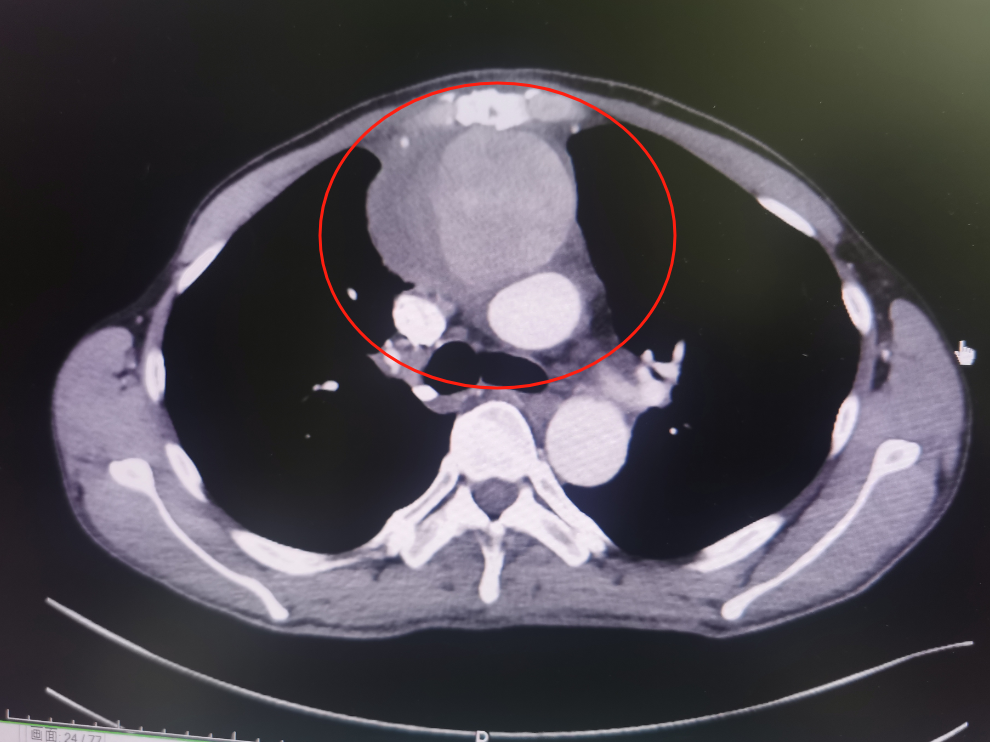

经检查,林先生系升主动脉假性动脉瘤破裂出血,也就是连接心脏最粗的一根动脉血管破裂出血,出血淤积在胸口位置流不出去,才让林先生出现了上述症状。

经过沟通,家属坚持手术,签署手术知情同意书后,介入·血管科为其实施主动脉造影+胸主动脉假性动脉瘤腔内覆膜支架隔绝术。支架随着林先生左侧腹股沟和腋窝两个切口缓慢向心脏移动,但意外还是出现了。由于升主动脉距离心脏近,血管粗、血流冲击大,加之患者胸主动脉破裂部位为人工血管,支架在释放时,被血流冲移位了。为了进一步减小伤害,斯光晏不得不终止手术。

斯光晏解释到:“该支架为进口支架,柔顺性、贴合性更好,出现支架移位风险小,是目前上市胸主支架性能最好的覆膜支架,患者升主动脉为人工血管,直径达35mm,目前在国内仅有一支备用支架(在北京市找到一支)。”

斯光晏教授、胡伟博士、袁罡博士、徐燕能博士从右侧股动脉入路,经鞘送入戈尔40-100mm覆膜支架至升主动脉,精确定位后,缓慢释放支架主体……

缓慢撤出支架输送系统后,造影见主体支架位置固定、展开良好,血流较术前缓慢。随后经胸超声引导下,向瘤腔注射凝血酶,见瘤腔内完全血栓化,血流信号明显减少,置入引流管,见少量淡血性液体流出,假性动脉瘤消失。历时2小时,手术顺利